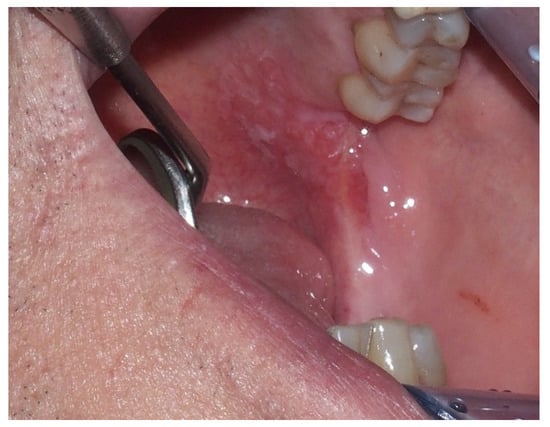

2.2. Erythroplakia